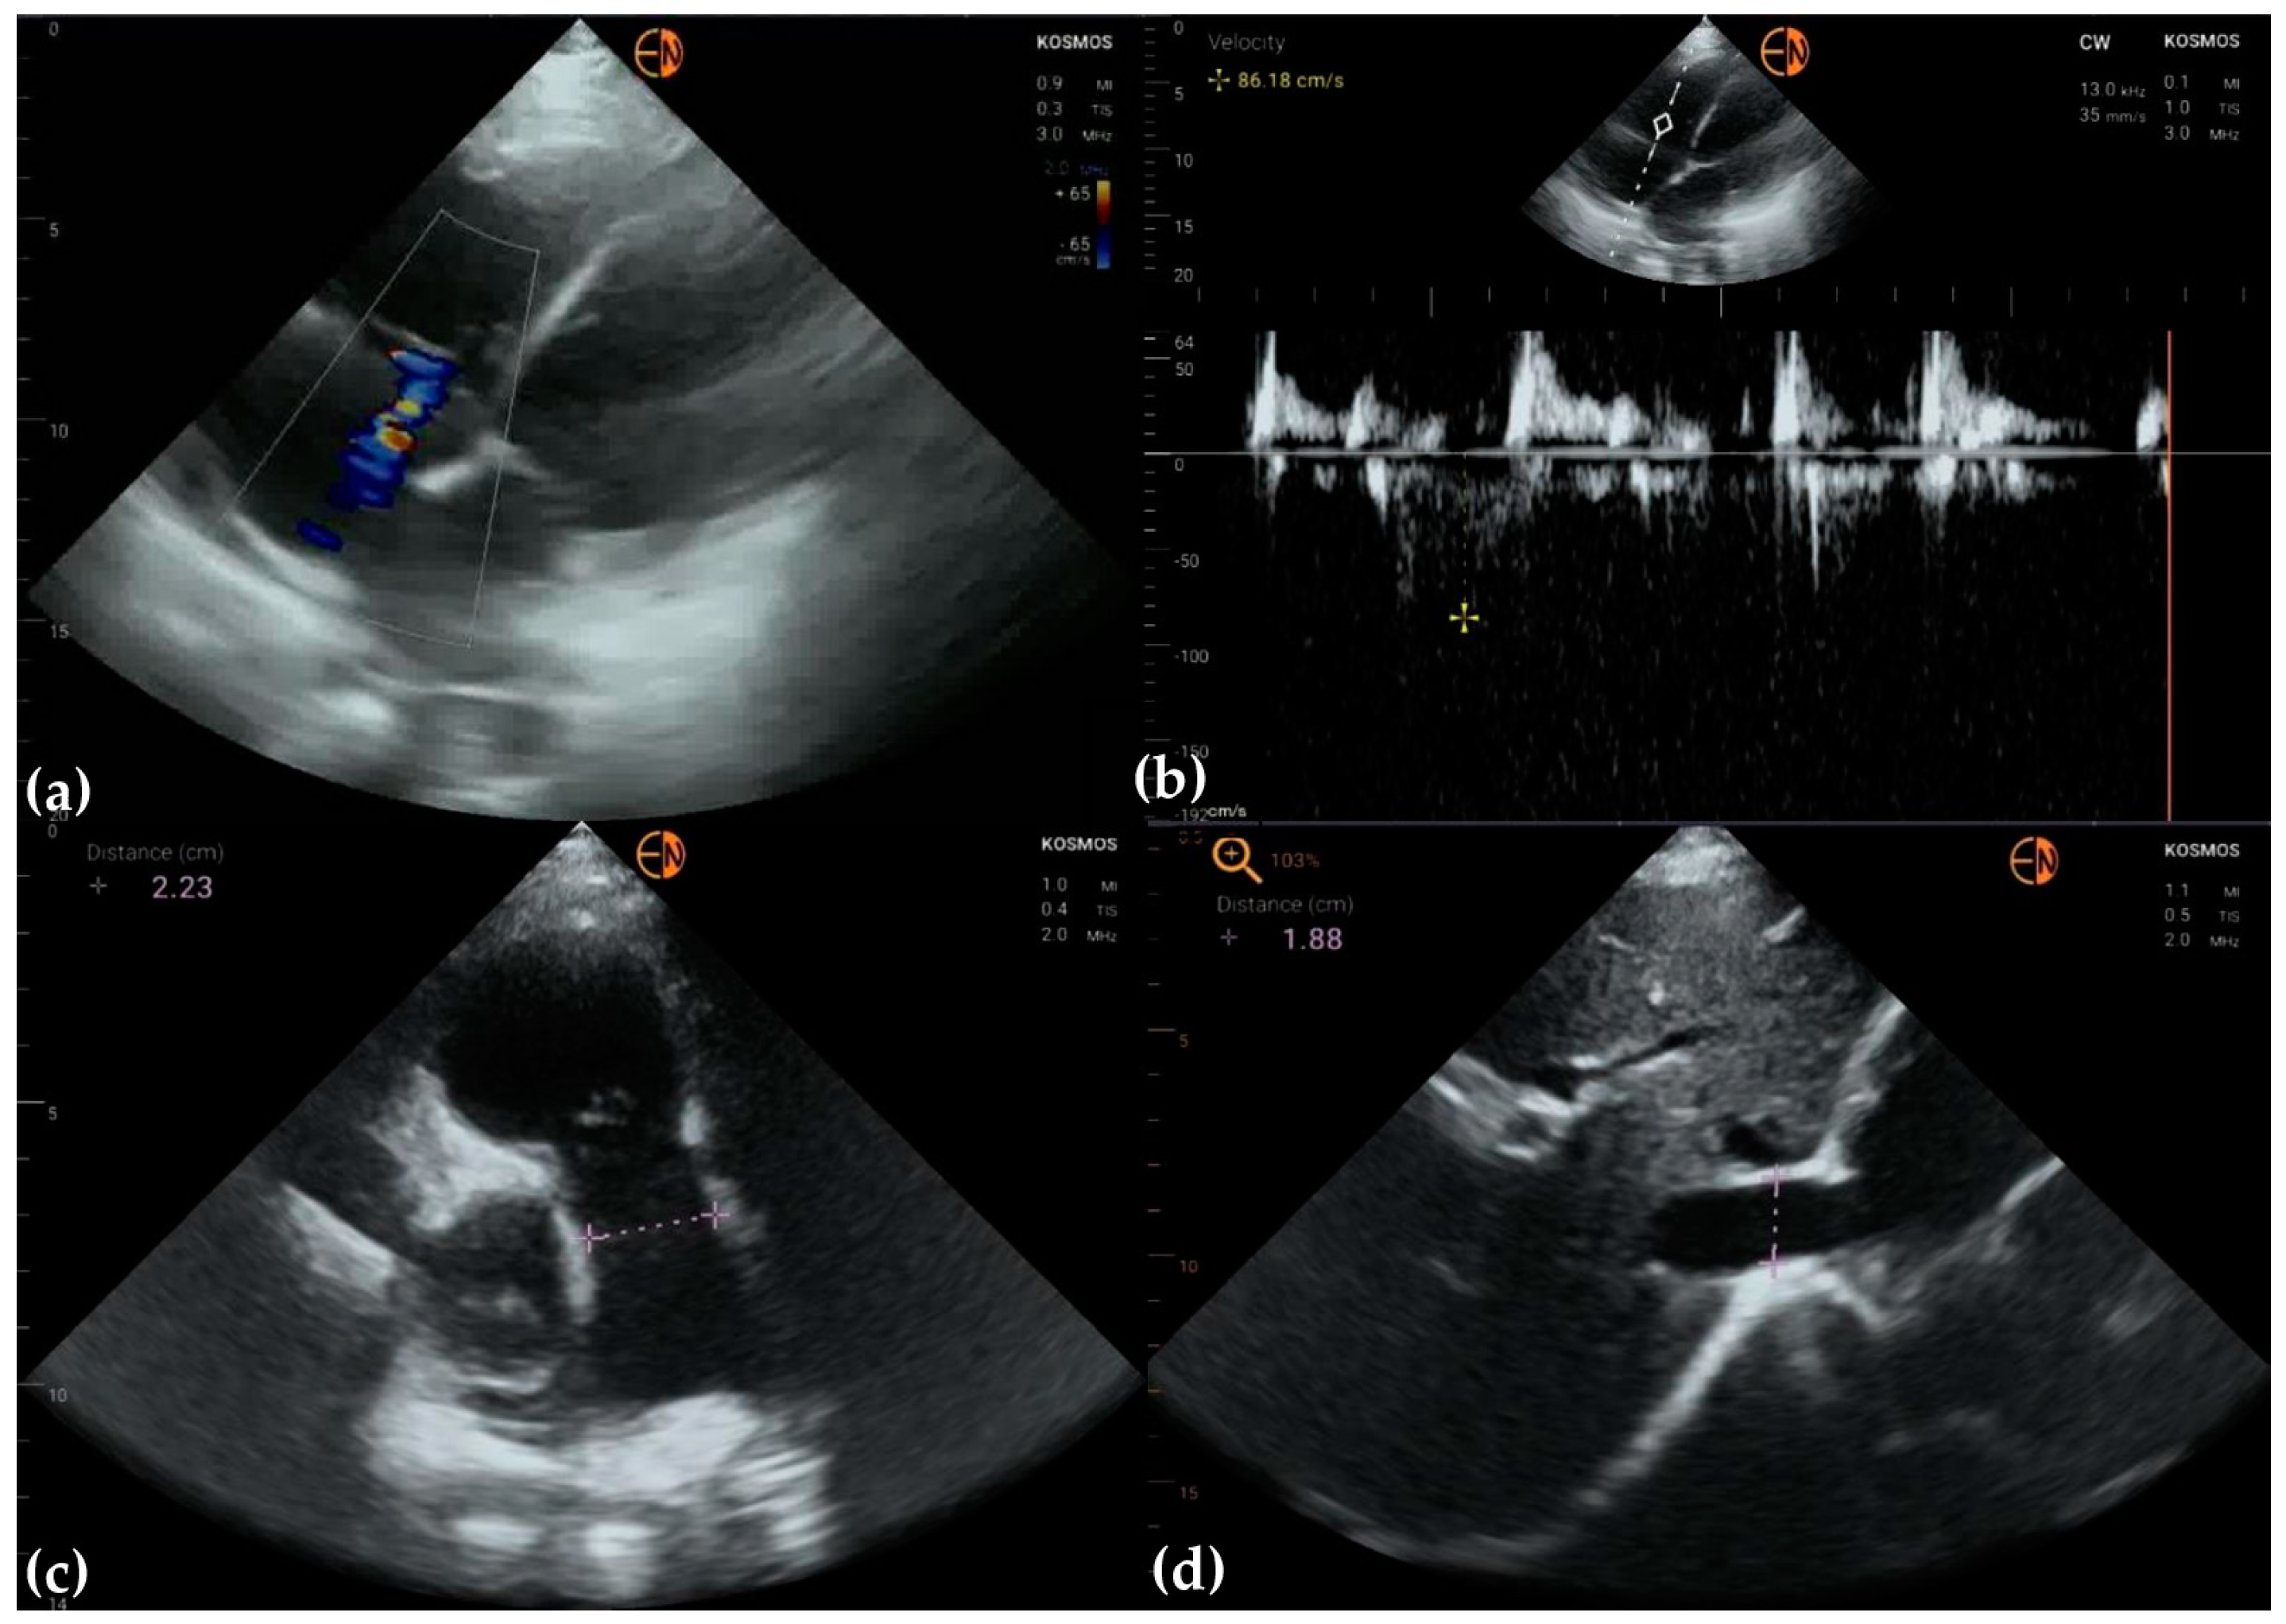

3.3. Valvular Stenosis and Regurgitation

3.4. Other Findings